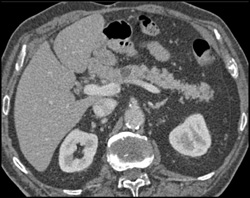

Pancreatic Laceration Due to MVA